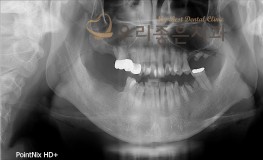

우리좋은치과 치아 상실 및 골소실 → 뼈이식 및 임플란트 보철 치료(김**2018...

No.300

임플란트

2019-05-31

1353